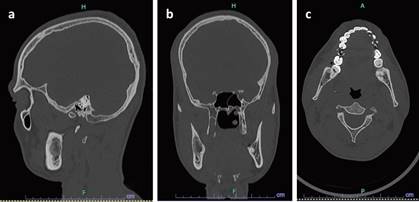

Imágenes por tomografía computarizada se observan 2 lesiones hipodensas aisladas una de la otra ubicadas en cuerpo (Fig. 2) y rama mandibular derecha (Fig. 3), una de ellas comprometiendo periapice de diente 18, ambas lesiones de 1.5 cm de diámetro aproximadamente.

Respecto a los estudios imagenológicos, se encuentran principalmente la tomografía computarizada (TC) y, en casos seleccionados, la resonancia magnética nuclear (RMN), quienes juegan un papel importante en el diagnóstico y manejo3. Es necesario considerar radiológicamente diagnósticos diferenciales con lesiones mandibulares radiolúcidas como el ameloblastoma, asimismo, diferenciarlos de los quistes foliculares, relacionados con la corona de piezas incluidas1.